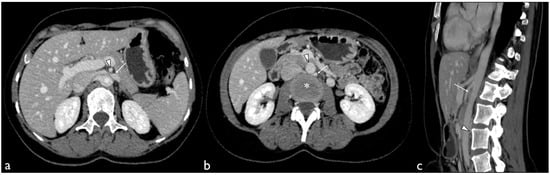

2. Case Presentation